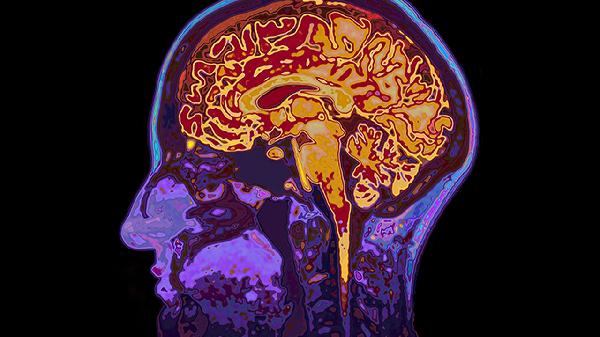

大脑缺氧的症状主要有头晕、头痛、注意力不集中、记忆力减退、意识模糊等,可通过吸氧、药物治疗、高压氧治疗等方式改善。大脑缺氧可能与高原反应、贫血、脑血管疾病等因素有关,建议及时就医明确病因。